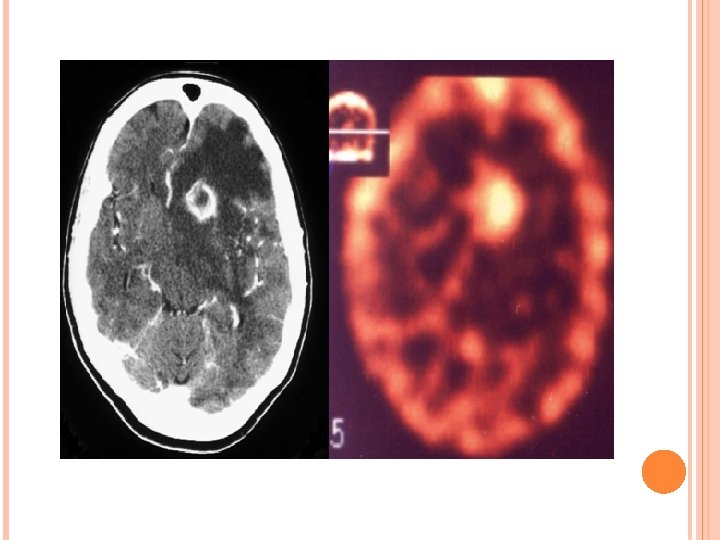

PRIMARY CNS LYMPHOMA IMAGING: CT-Typically a solitary hyperdense mass on NECT however multifocal in 50% cases. MR-Iso to hypointense on T 1 W and T 2 W image with diffusion restriction. Enhancement pattern are variable homogenous/heterogenous/ring like. Edema and mass effect in half of the lesion. Increase choline peak on MRS and increase Thallium uptake on SPECT.

Primary CNS lymphoma High choline peak. Lactate peak in necrotic component.